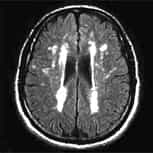

我們是一家位於西班牙巴塞隆納的國際專科醫療中心,不設分院,專注於精準且高品質的醫療照護。我們採用微創手術從病因治療Arnold-Chiari I型症候群、特發性脊髓空洞症與脊柱側彎等相關疾病,致力於為來自世界各地的患者帶來更安全、更有效的治療選擇。